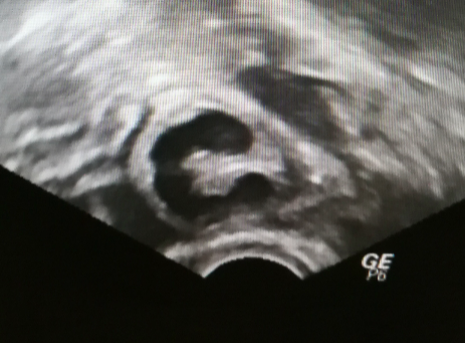

盆腔液性暗区

图片

图源:参考文献

根据产生原因,盆腔积液分为生理性及病理性两大类。

生理性:排卵期、月经期可有生理性盆腔积液。盆腔处于腹腔最低的部位,当盆腹腔脏器有少量渗出液、漏出液或破裂出血时,液体会首先聚积在盆腔,从而形成盆腔积液。这些情况属于生理性的,不需要临床治疗。

病理性盆腔积液:

❶  盆腔炎:盆腔炎是指上生殖道及其周围组织的炎症,主要有子宫内膜炎、输卵管炎、输卵管卵巢脓肿、盆腔腹膜炎,其中输卵管炎最常见,大多发生在生育年龄妇女。

❷  结核性盆腔炎:输卵管结核最为多见,输卵管结核常合并盆腔腹膜结核,腹膜及盆腔脏器表面布满粟粒状结核病灶,产生大量的渗出液聚积在盆腔。

❸  异位妊娠:输卵管妊娠流产或破裂,则会造成输卵管壁破裂出血,血液聚积在子宫直肠陷凹而形成盆腔积液。超声检查仅能显示盆腔积液,不能显示积液是否是血液。异位妊娠患者多有不规则阴道出血、下腹痛,尿妊娠试验阳性。

❹  卵巢及输卵管恶性肿瘤:发生卵巢及输卵管恶性肿瘤,腹水一般较多,超声及磁共振检查在附件区发现占位,肿瘤指标等检测有助于诊断及鉴别诊断。

如果是病理性积液,积液量都会在 100 ml 以上,最好是对因治疗。